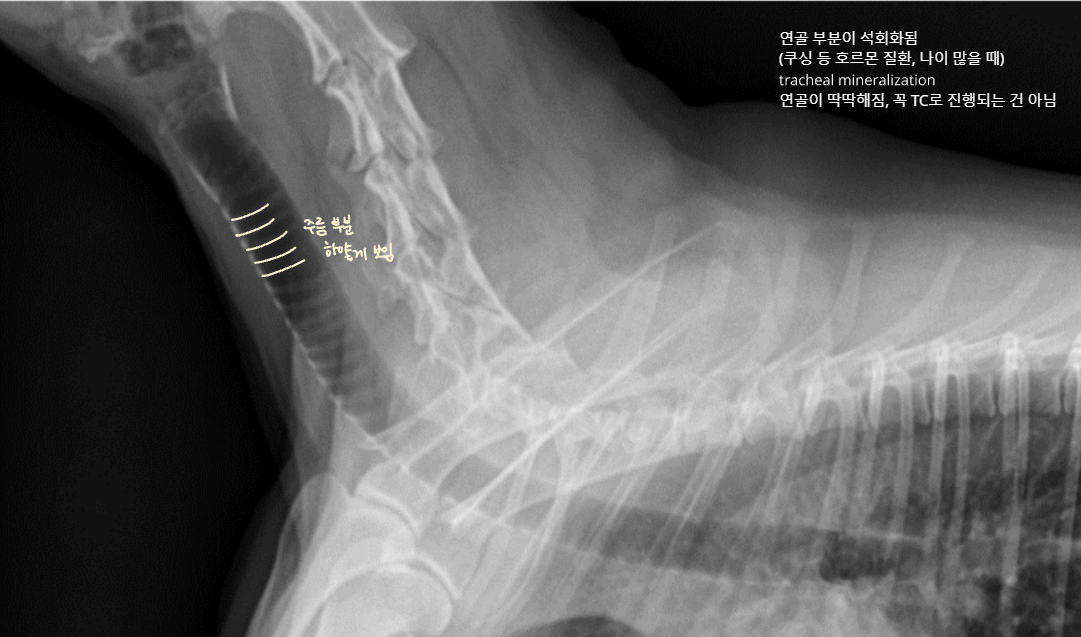

Tracheal mineralization (연골 경화)

- 노화, 호르몬 질환(Cushing 등)